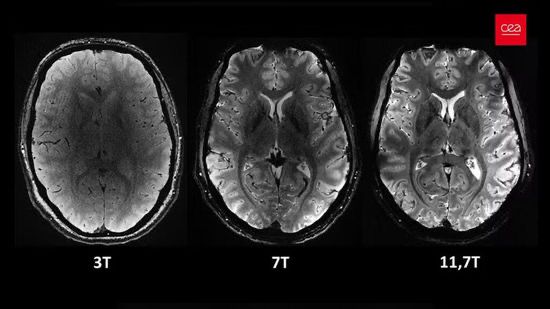

İnsan beyninin ən aydın görüntüsü yayımlanıb